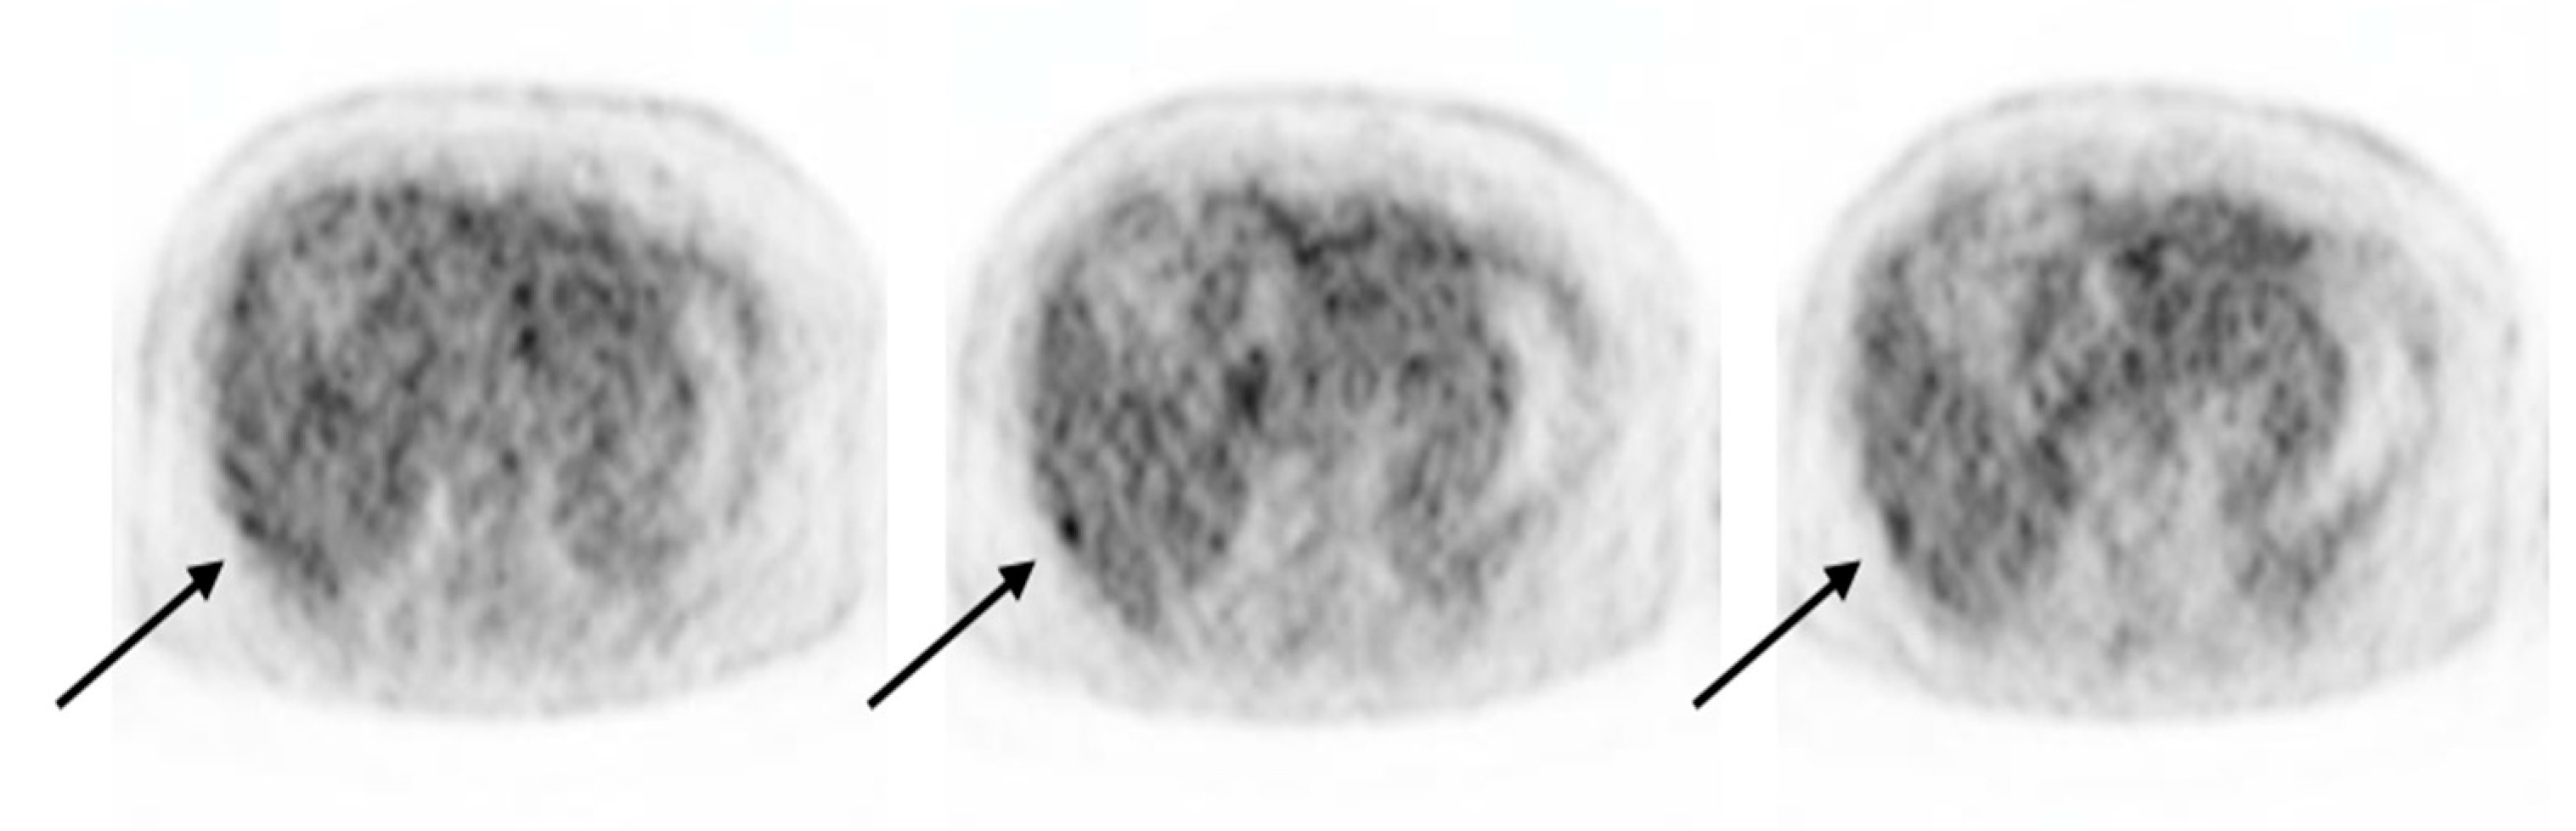

Detection of Hepatic Metastasis from Early Delayed Images of Modified Dual-Time-Point F-18 FDG PET/CT Images in a Patient with Breast Cancer